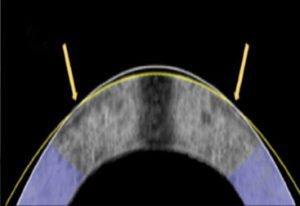

ЕМП сплющило цю рогівку кролика, показану на поперечному перерізі, від її початкової форми (біла лінія) до скоригованої (жовта лінія).

Дослідники випробували цей метод на 12 очах кроликів, 10 з яких лікували так, ніби вони мають міопію, або короткозорість. Лікування успішно змінило форму рогівки таким чином, що світло краще фокусувалося на сітківці, і клітини очних яблук не були пошкоджені в процесі.